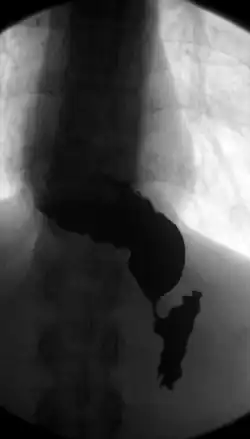

![]() R-контрастный снимок сульфатом бария, видны замедление поступления жидкости в полость желудка через суженный просвет сфинктера и скопление её в расширенном просвете пищевода S-образной формы | |

| 4 стадия | Отмечается выраженное рубцовое сужение пищевода в сочетании с его расширением, S-образной деформаций и развитием осложнений - эзофагита и параэзофагита. |